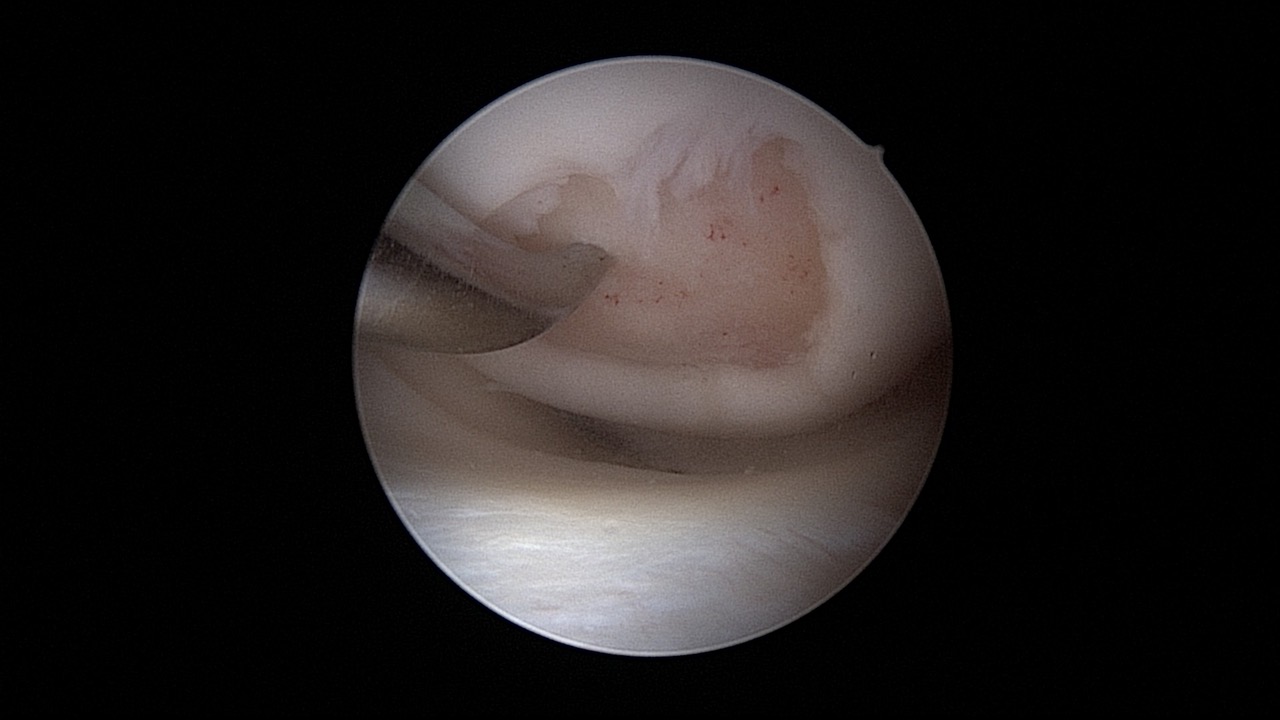

#034: Inside-Out-/Out-In-Meniskusnaht

Operateur: Dirk Holsten | Kommentar: Matthias Feucht, Stefan Hinterwimmer, Philipp Niemeyer

Provided by

Winglet

Date

Oct 2018

Format

TechTip

Price

0.99 €

Arthroscopy

Knee

Sports Medicine